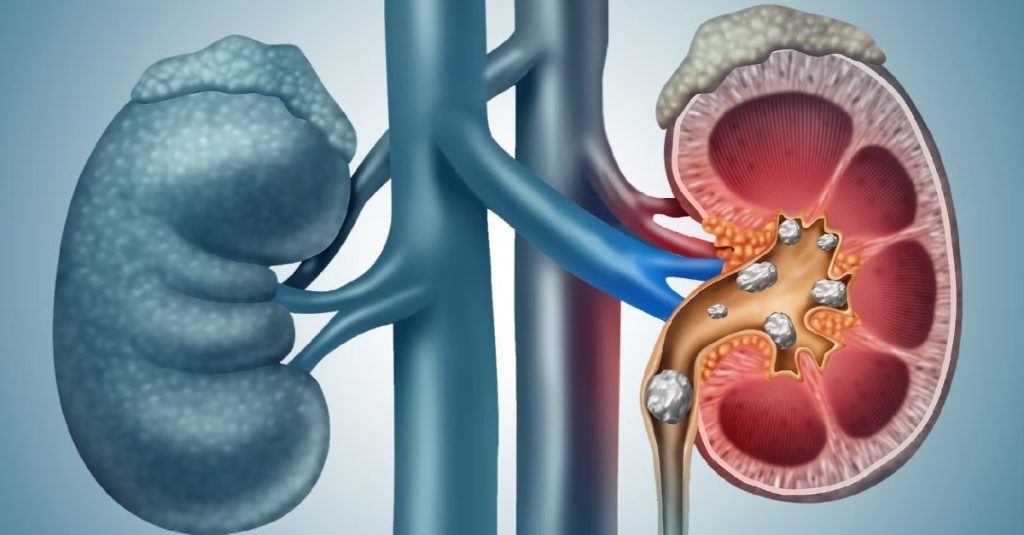

What Are Kidney Stones?

Kidney stones are solid crystal-like masses that develop when urine becomes concentrated with minerals and salts. Normally, urine contains substances that prevent crystals from sticking together. However, when there is an imbalance, these substances can no longer prevent crystal formation, leading to stone development in the kidneys or urinary tract.

Depending on size, kidney stones can be as small as a grain of sand or as large as a golf ball. Small stones often pass out of the body without causing much trouble, but larger stones can block urine flow and result in intense pain.